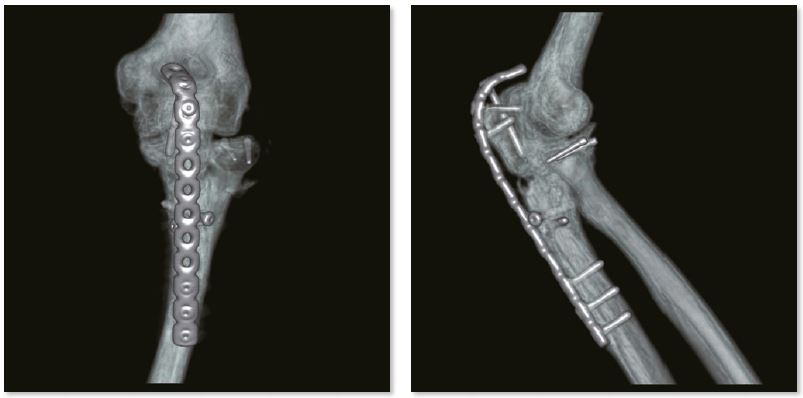

Лікоть з внутрішньою фіксацією

Металеві артефакти більше не є перешкодою для точної післяопераційної оцінки переломів за допомогою пристроїв внутрішньої фіксації. Незрощення перелому проксимального відділу променевої кістки дуже детально показано на реконструкції SEMAR.

3D зображення ліктьового суглоба

Звичайне зображення

Зображення з SEMAR